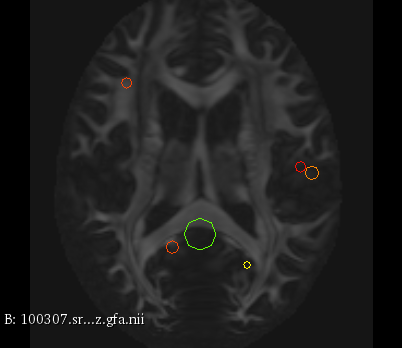

Figure 3 provides a scale-space visualization of feature matches for a single pair of MZ twins and NT siblings, where scale information is represented using the circle radius. Note that circles represent the intersection of 3D spheres with the visible slice and, thus, non-intersecting features are hidden in this 2D visualization.

It can be seen that different image modalities generally result in distinct, complementary feature correspondences throughout the brain, allowing a rich characterization of both anatomical and connectivity structure. In T1 and T2 images, features are mainly located in the frontal lobe, corpus callosum and brain stem. Smaller-scale features are also visible along various cortical regions, as well as in sub-cortical structures near the basal ganglia. Although highly correlated, T1 images show significantly more feature matches than T2 images. Moreover, images based on diffusion measures have less matches than in structural modalities. These matches are located mostly inside or near to white matter: larger-scale features in the corpus-callosum, and smaller-scale ones in the brain stem and along white matter bundles. While not shown in the figure, the set of matches found by combining two modalities (e.g., T1 + T2) generally corresponds to the union of those obtained with these individual modalities.

Comparing different sibling types, we observe a greater number of matches between MZ twins than NT siblings. This observation, which is easier to visualize in T2 and GFA images, is consistent with other analyses on twin datasets. In terms of feature location and scale, no obvious pattern can be seen when comparing these two sibling types. However, a more detailed analysis would be required to validate this assertion.